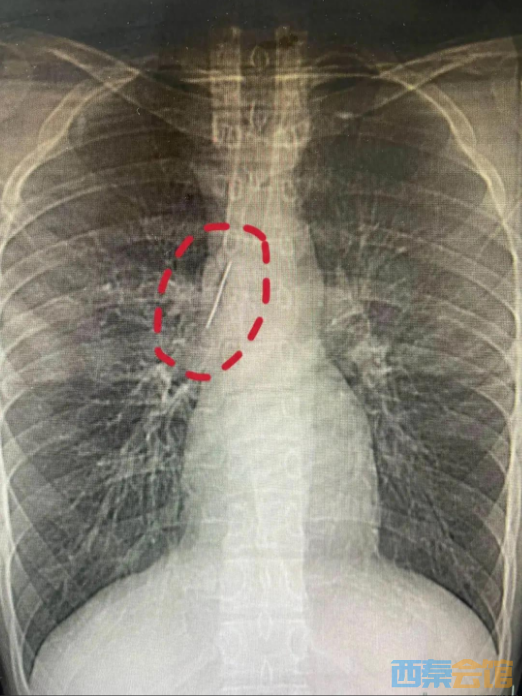

不久前,怀揣军旅梦的他,满怀期待参加征兵体检,没想到胸片结果让医生当场警觉:他的胸腔内有一处明显金属高密度影,形态细长,像一根针。

进一步CT检查确认,异物像是一根金属针,斜插在肺组织内,针尖紧紧贴着胸主动脉、上腔静脉等体内重要血管,稍有位移就可能刺破血管引发致命大出血。